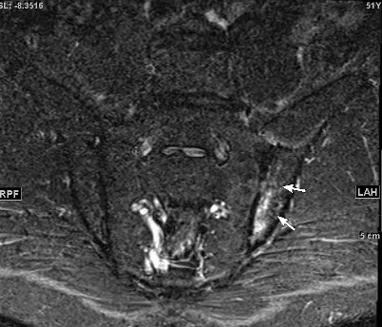

中年男性に発症した、単関節炎とその周囲炎(Psoriatic onycho-pachydermo periostitis:POPP)。血清反応陰性で、尿酸値は正常。尋常性乾癬あり、足趾に爪病変をみとめた。また詳細な病歴聴取にて2週間前から炎症性腰背部痛を認めたため、脊椎の側面および骨盤正面単純X線検査を行うも異常なし。その後仙腸関節および全脊椎MRIを施行し(図3a:T2FS, b:T2FS, c:T1)、左仙腸関節に骨髄浮腫の所見を数スライスにわたりみとめ、X線基準を満たさない体軸性脊椎関節炎(体軸性乾癬性関節炎)と診断した。

ASAS/SPARTANから、2024年体軸性脊椎関節炎を疑ったときに施行するMRI撮像法についての標準化の提案があった(4つの撮像法:1.S2椎体の背側骨皮質に平行した斜冠状断でT1強調画像, 2.同部位でSTIR or T2強調脂肪抑制像、3.同部位のT1強調3Dグラデーションエコー(T1強調脂肪抑制)、4.左記斜冠状断に垂直な斜軸断でSTIR or T2強調脂肪抑制像)(参考文献)

図3a,b,c 仙腸関節MRI